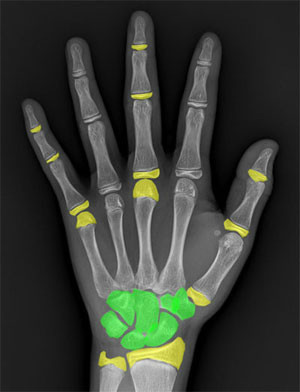

人的生長發(fā)育,表現(xiàn)為生活年齡和生物年齡。生活年齡是從出生開始計(jì)算的年齡(也就是我們常說的歲數(shù)),生物年齡是根據(jù)正常人體生理學(xué)

和解剖學(xué) 的發(fā)育狀態(tài)所推斷出來的年齡。目前,應(yīng)用最廣泛用來評(píng)價(jià)生物年齡的方法就是測骨齡。骨齡顧名思義就是骨骼的年齡,通過觀察骨化

中心的大小、形態(tài)、結(jié)構(gòu)和相互關(guān)系的變化來判斷體格和生理的發(fā)育程度。通過對(duì)發(fā)育程度進(jìn)行統(tǒng)計(jì)處理,以年齡的形式,以歲為單位進(jìn)行表達(dá)的生物學(xué)年齡。

(手的骨骼發(fā)育示意圖)

骨齡檢測通就是對(duì)被測者的手部和腕部進(jìn)行X光攝片,通過觀察手部的腕骨、掌骨、指骨的形態(tài)特點(diǎn)進(jìn)行骨齡判斷。